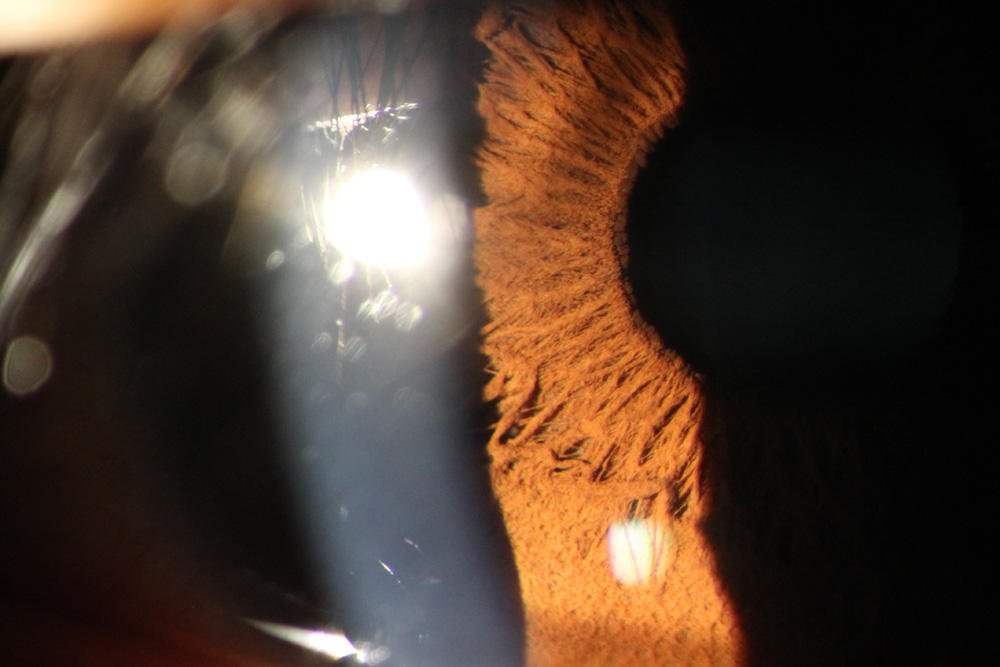

When choosing the best eye photography machine for clinical or research use, prioritize models with high-resolution imaging, adjustable lighting, and compatibility with electronic health records (EHR). A top recommendation is to select a digital fundus camera with non-mydriatic capabilities if you need to capture clear images without pupil dilation—ideal for patient comfort and efficiency in high-volume practices 1. Look for systems offering automated alignment, built-in image stabilization, and telemedicine integration, especially if serving remote areas or planning scalable screening programs. For most professionals, a mid-range model balancing precision, ease of use, and service support delivers the best long-term value.

About Eye Photography Machines

An eye photography machine, commonly known as a retinal or fundus camera, is a specialized medical device designed to capture detailed images of the interior structures of the eye, including the retina, optic disc, macula, and blood vessels. These devices are essential tools in ophthalmology, optometry, and diabetic eye screening programs. Modern versions often integrate digital sensors, LED illumination, and software analytics to enhance diagnostic accuracy.

Typical usage scenarios include routine eye exams, monitoring progression of diseases like glaucoma and diabetic retinopathy, pre- and post-surgical assessments, and population-based vision screening initiatives. Some advanced models also support anterior segment imaging, enabling comprehensive anterior and posterior eye evaluation from a single platform.